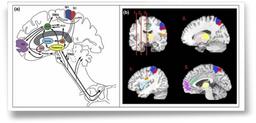

| | En 1812, Arthur Schopenhauer écrivait : " La vie oscille comme un pendule de droite à gauche, de la souffrance à l'ennui. " Toute la philosophie Taoïste tourne autour de cet équilibre entre deux forces contraires, le Yin et le Yang, qui loin de s'annuler déterminent le mouvement qui est la Voie, représentée par le Vide Médian. Plus important encore est le fait que la douleur est en nous. Notre organisme dispose de tout l'équipement neuronal apte à transformer une perception, la nociception, en sensation, la douleur, et en sentiment, la souffrance. Le cheminement de la nociception à la souffrance s'opère grâce à une intégration progressive de l'influx nerveux de la périphérie à la corne dorsale de la moelle, des cordons spino-thalamiques au thalamus, aux structures sous corticales pour se projeter finalement au niveau du cortex. Tout au long de ce parcours par des voies dédiées, le message d'abord purement nociceptif va se charger de tout ce qui fait la personnalité de l'individu, en particulier la mémoire de son vécu antérieur, coloré de tous les aspects de sa psychologie, de sa culture et de ses croyances. |

| | Du point de vue psychologique, la douleur est langage. Elle exprime un mal-être et attends de l'autre une empathie, une compréhension sinon un partage de la souffrance. Cette empathie se manifeste à la vue de la souffrance et même les sujets incapables génétiquement de souffrir sont capables d'illuminer en imagerie fonctionnelle, IRM et tomographie à émission de positrons (pet-scan), les zones du cortex impliquées dans l'intégration de la douleur, comme l'ont démontré Danièla Simon et collaborateurs. En revanche, si Alain pense que : " les maux d'autrui sont toujours lourds à porter ", La Rochefoucault en revanche, estime que " nous avons toujours assez de force pour supporter les maux d'autrui ". La relation de l'individu lui-même à sa propre douleur n'est pas univoque. La douleur c'est la vie. " Toute existence n'est que douleur. A l'origine de cette douleur universelle est la soif d'exister, la soif de plaisir et même la soif de mourir. Attendez tout de vous-même " proclame Bouddha dans son premier sermon. François Mauriac écrit : " Tu t'éveilles et d'abord tu cherches la place de ta douleur pour t'assurer que tu existes " ce que constate JMG Le Clézio dans " Le jour où Beaumont fit la connaissance de sa douleur " où il décrit l'appropriation de la douleur par celui qui souffre : " J'ai besoin de ma douleur, maintenant je ne suis plus rien que par elle. Et je l'aime. " Cesare Pavese lui fait écho : " Au moins pendant que l'on souffre on ne s'ennuie pas. " |

|  | | Voies de la douleur et localisation des projections cérébrales par PET.scan. |

|  | De la nociception à la souffrance. Schéma : Philippe Scherpereel. |